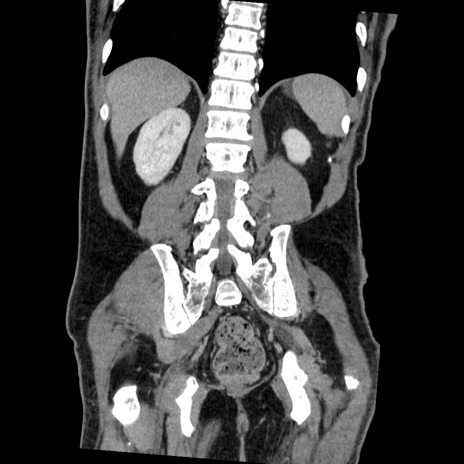

症例22(冠状断像)

【症例】50歳代男性

【主訴】腹痛

【現病歴】AVMからの被殻出血のため回復期リハ病棟入院中。 本日午後3時頃急に下腹部痛が出現した。

【既往歴】AVM、被殻出血、虫垂炎、高血圧

【身体所見】意識晴明、左半身不全麻痺、会話の理解は良好、36.5°C、腹部:膨隆、全体に板状硬、下腹部正中に圧痛点あり、反跳痛-、筋性防御不明、右下腹部にope scar

【データ】WBC 9400、CRP 0.06